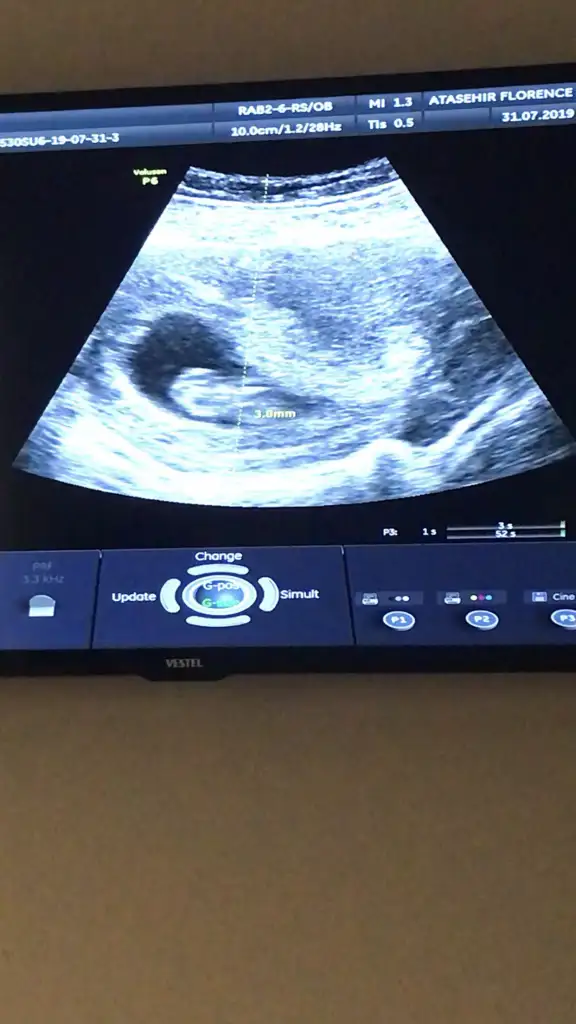

gözün aydın canım çok sevindim, hep böyle güzel haberler alalım inşallahMerhaba kızlar kontrolum vardi bugün doktor herşey normal dedi çok şükür. Zipliyordu eli kolu durmuyordu zor ölçtü hocaCinsiyet için bir ay sonra kesinlessin o zaman söyleyim dedi. ikili için kan verdim tsh t4 icin de sabah kan vericem. Sonuç raporunu koyuyorum buraya bilgili arkadaşlardan yorum alırım.